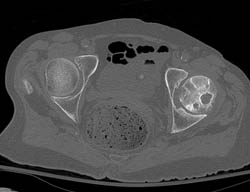

DIEP Flap Planning